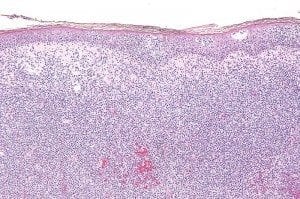

lymphoma.jpg